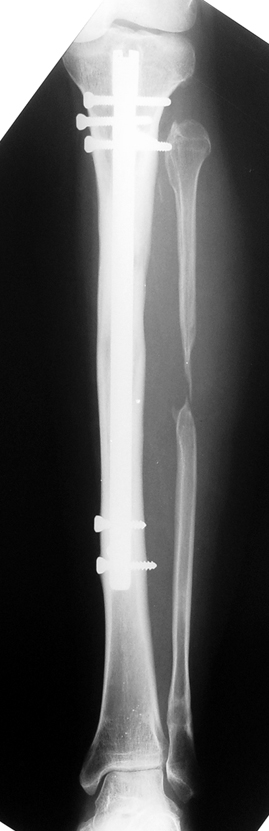

Installment of the intramedullary nail and osteotomy:

The application of the external fixator: Three Schanz screws are placed distally and three screws are placed proximally. At least 1 mm of distance shall remain between the screws and the nail.

Postoperative care: Distraction is commenced at day 10. 0,25 mm of lengthening is perfomed 4 times daily (every 6 hours). Hip and knee joint motion exercises begin at 1-2. day postoperatively. For many years, the treatment of lower extremity shortness has been very hard for the patient and the surgeon. The techniques developed after the introduction of Ilizarov’s distraction osteogenesis concept have pioneered a new era, and have been considered to be procedures in which previous complications are encountered much less frequently.

In selected cases, we prefer to use a combination of a unilateral dynamic axial fixator and an interlocked intramedullary nail, in order to protect the length and alignment after the completion of the lengthening procedure. As a prerequisite for this technique, the narowest diameter of the medullary cavity shall be wider than 7 mm and the length of the nail segment distal to the osteotomy site shall be at least 8 cm. after the completion of the lengthening procedure.The intramedullary nail neutralizes shear and bending forces on femur during lengthening, shortens external fixation time, and protects newly formed bone against fractures. In our series, subtrochanteric osteotomy was performed in one case. No varus angulation occured despite the intramedullary nail.